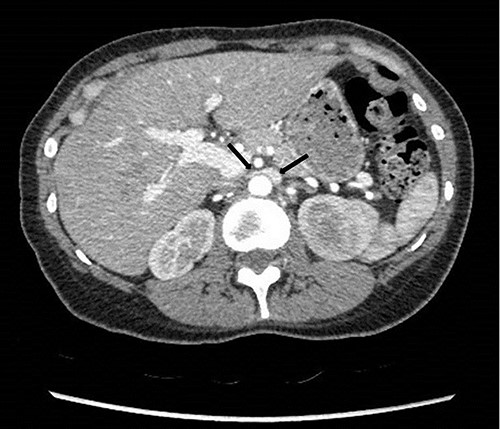

She underwent a flexible ureterorenoscopy 2 months later which further demonstrated no cause for hematuria within the collecting system. An ECHO cardiography was performed to out rule an embolic event to the kidney due to the patchy perfusion noted and was normal. A repeat CT angiogram showed resolution of the congestion of the left kidney, but a narrow LRV as before (Fig. 8).

Computed tomography angiogram 6 months later showing pre-compressed LRV (right arrow); and compressed LRV (left arrow), but resolution of the congestion and swelling of the left kidney.